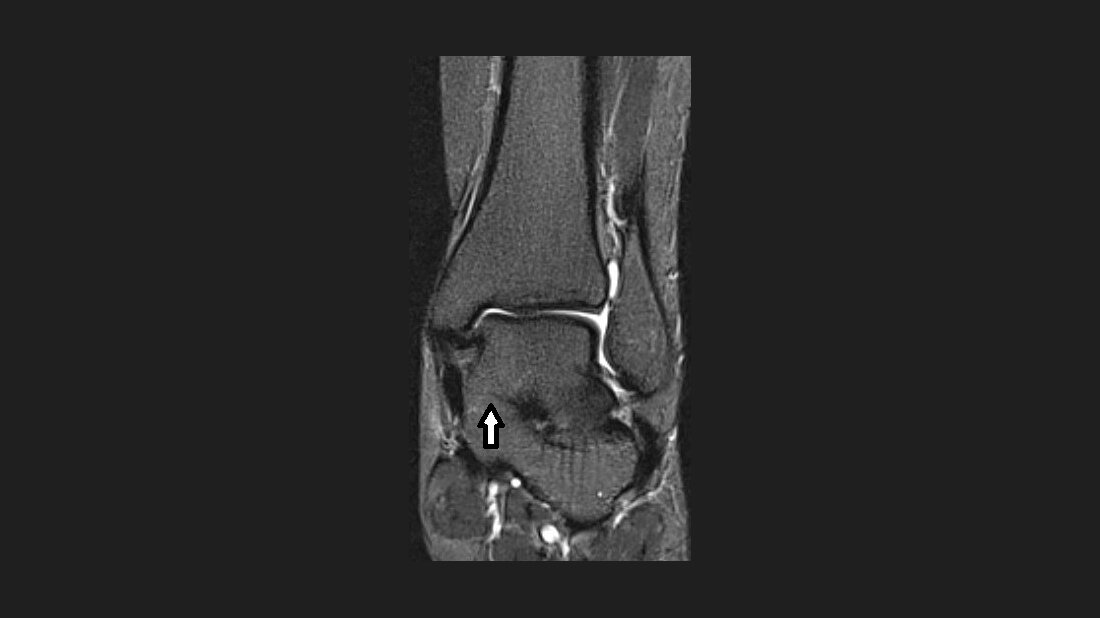

Anomalien und Normvarianten: Skelettale Veränderungen 3.32 – Talokalkaneare Koalition

Die talokalkaneare Koalition ist eine seltene pathologische Verbindung des Talus mit dem Fersenbein. Die talare Koalition spiegelt eine abnorme fibröse, kartilaginäre oder knöcherne Verwachsung zwischen 2 oder mehreren tarsalen Knochen wider.

Talocalcanear coalition is a rare pathological union of the talus and calcanear bones. Tarsal coalition refers to an abnormal fibrous, cartilagenous, or bony connection that develops between two or more tarsal bones.